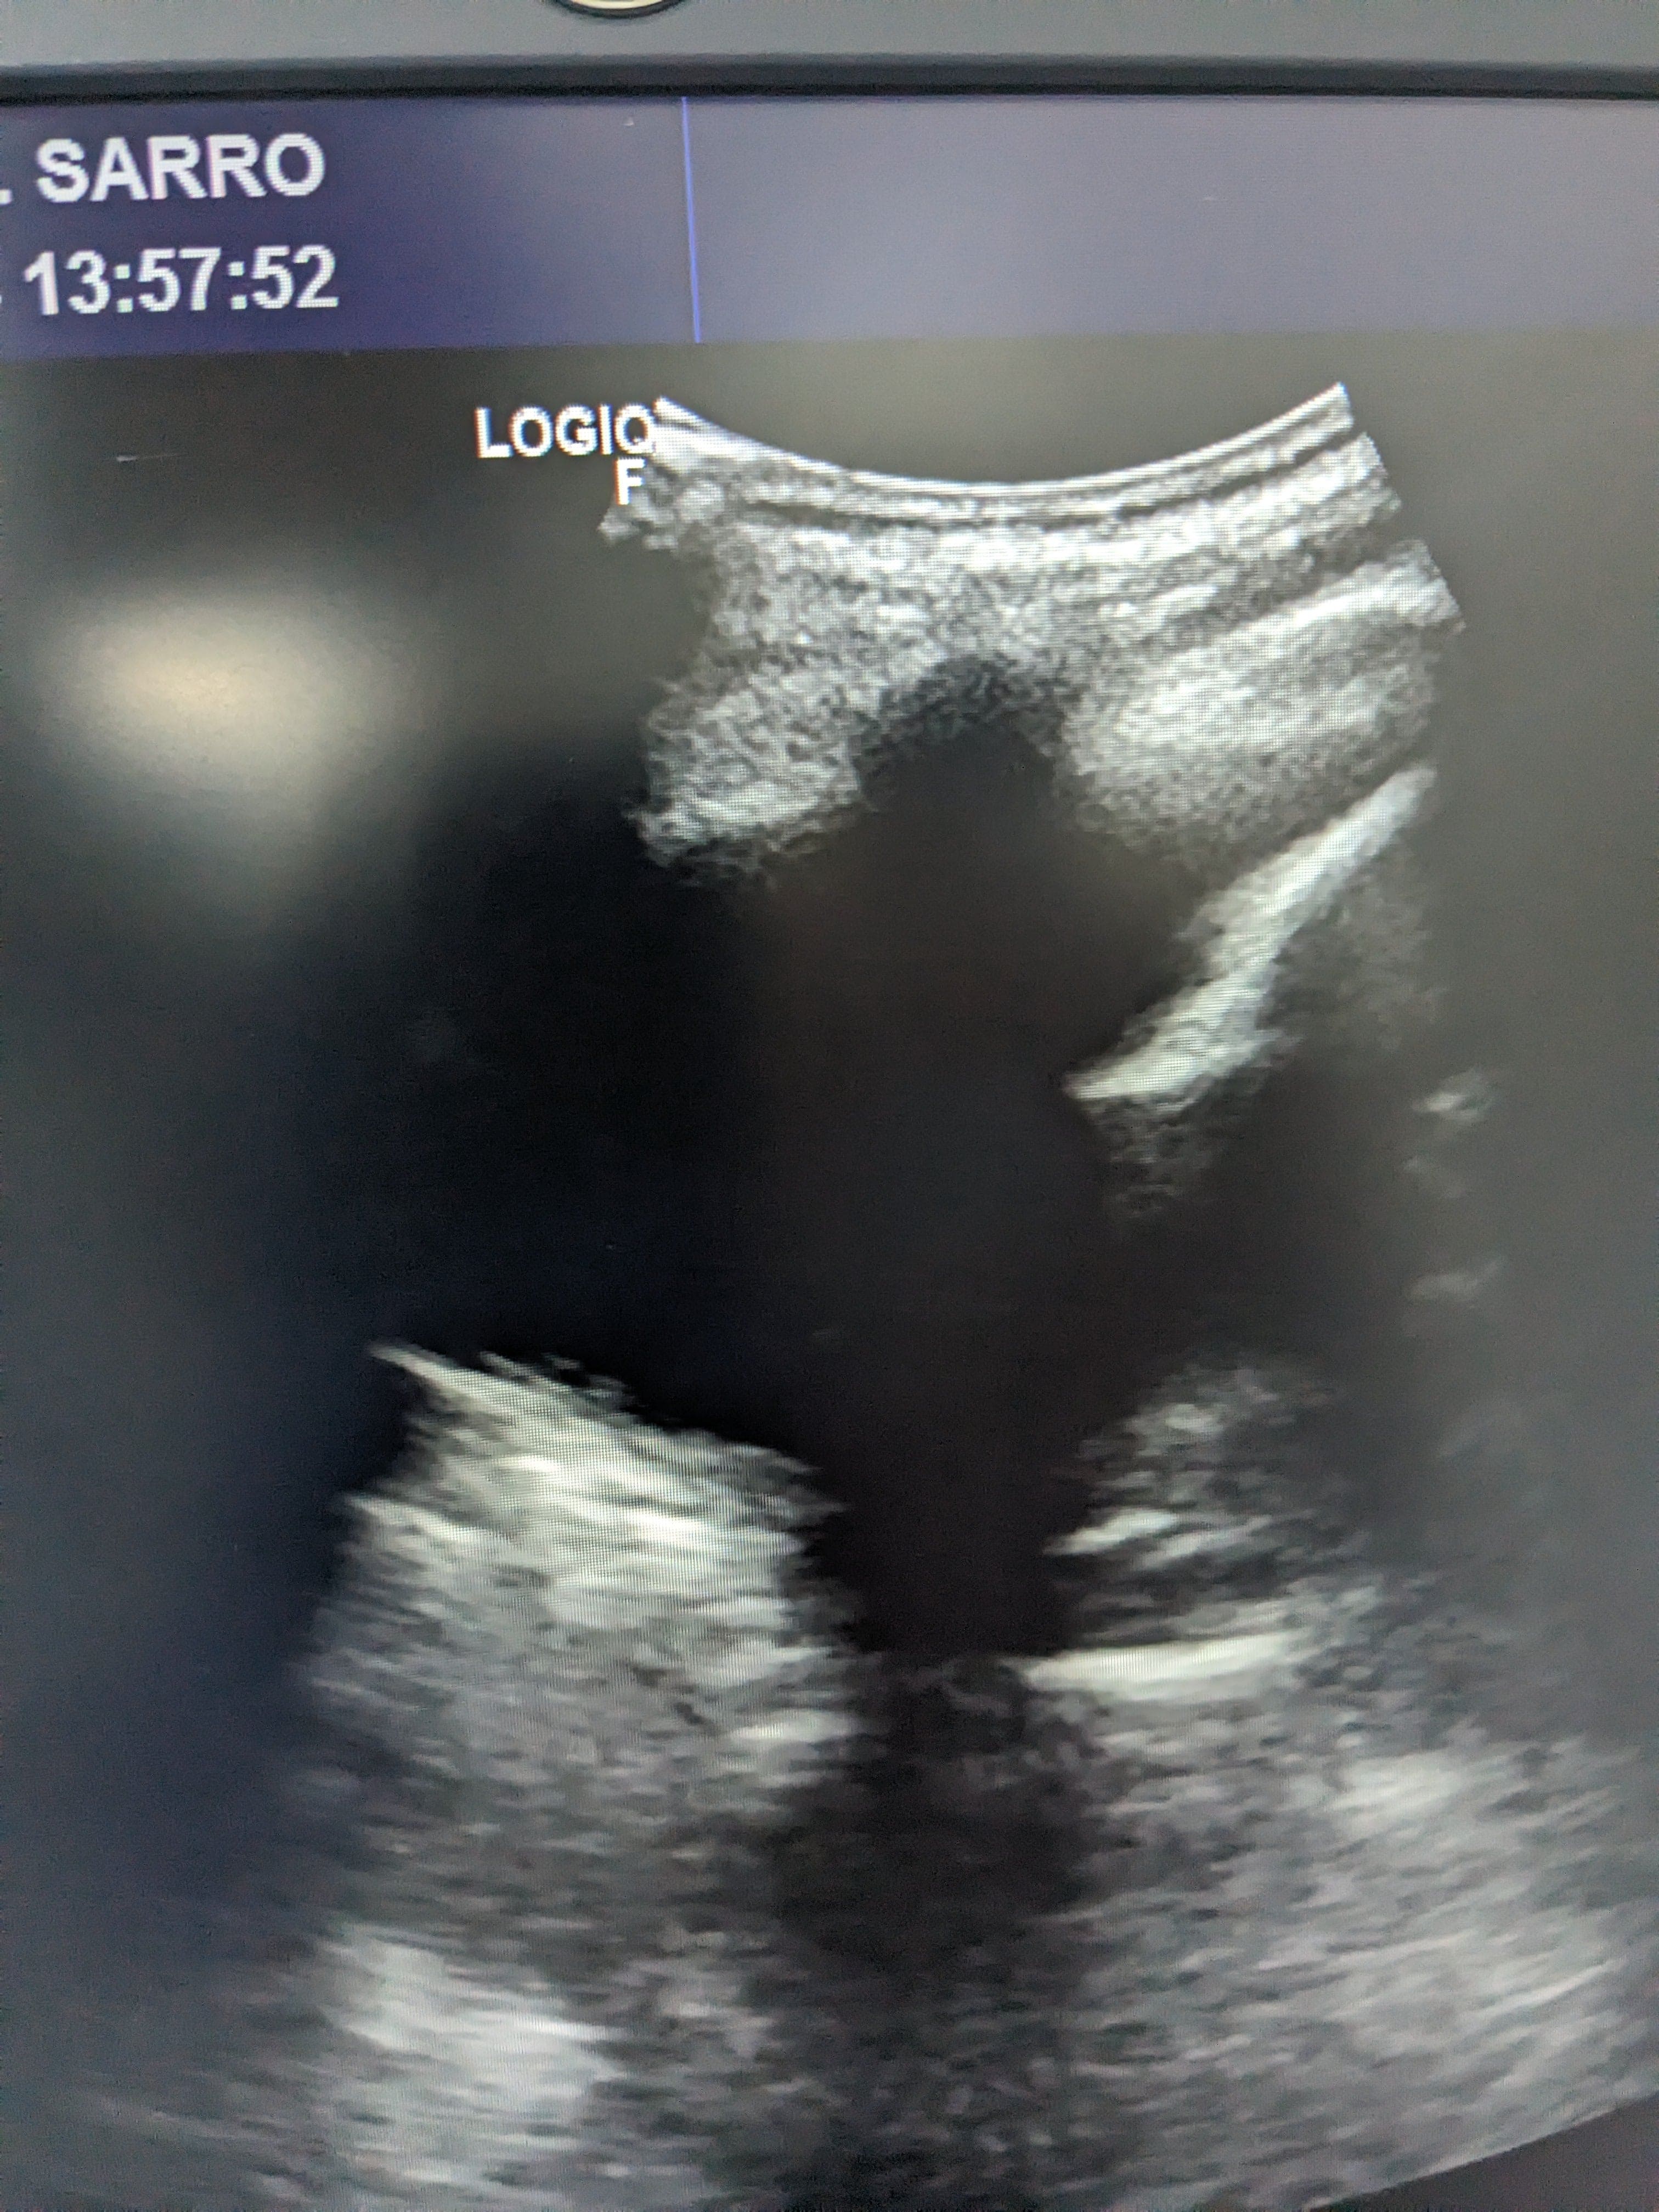

Se hace ecografía clinica en la consulta de atención primaria, observamos derrame pleural en pulmón izquierdo hasta medio campo pulmonar.